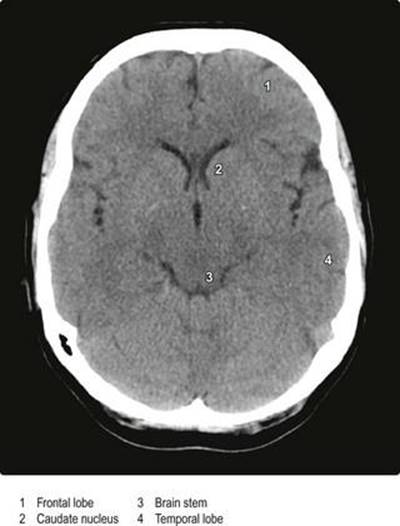

نورورادیولوژی شامل تعدادی تکنیک است که میتواند برای به دست آوردن تصاویر ساختاری و عملکردی از سیستم عصبی مرکزی و ساختارهای اطراف استفاده شود. تصویربرداری معمولی با اشعه ایکس بر روی جمجمه و ستون مهرهها اعمال میشود، در حالی که تصاویر ساختاری مغز و نخاع با استفاده از توموگرافی کامپیوتری (CT؛ شکل ۱.۴۳) و تصویربرداری تشدید مغناطیسی (MRI؛ شکل. ۱.۴۴) به دست میآید. تصاویر عملکردی از جریان خون منطقهای مغز، متابولیسم مغزی و اتصال لیگاندهایی مانند داروها به مغز را میتوان با استفاده از توموگرافی کامپیوتری با گسیل تک فوتون بهدست آورد (SPECT; شکل ۱.۴۵) و توموگرافی گسیل پوزیترون (PET). در رادیولوژی متضاد، یک محیط مات به شریانها یا وریدها (آنژیوگرافی) تزریق میشود تا رگهای خونی را مشخص کند (شکل ۱.۴۶).

شکل ۱.۴۳ اسکن محوری کامپیوتری (CT) سر.

شکل ۱.۴۳ اسکن محوری کامپیوتری (CT) سر.

(با اجازه پروفسور PD Griffiths، واحد دانشگاهی رادیولوژی، دانشگاه شفیلد، شفیلد، انگلستان).